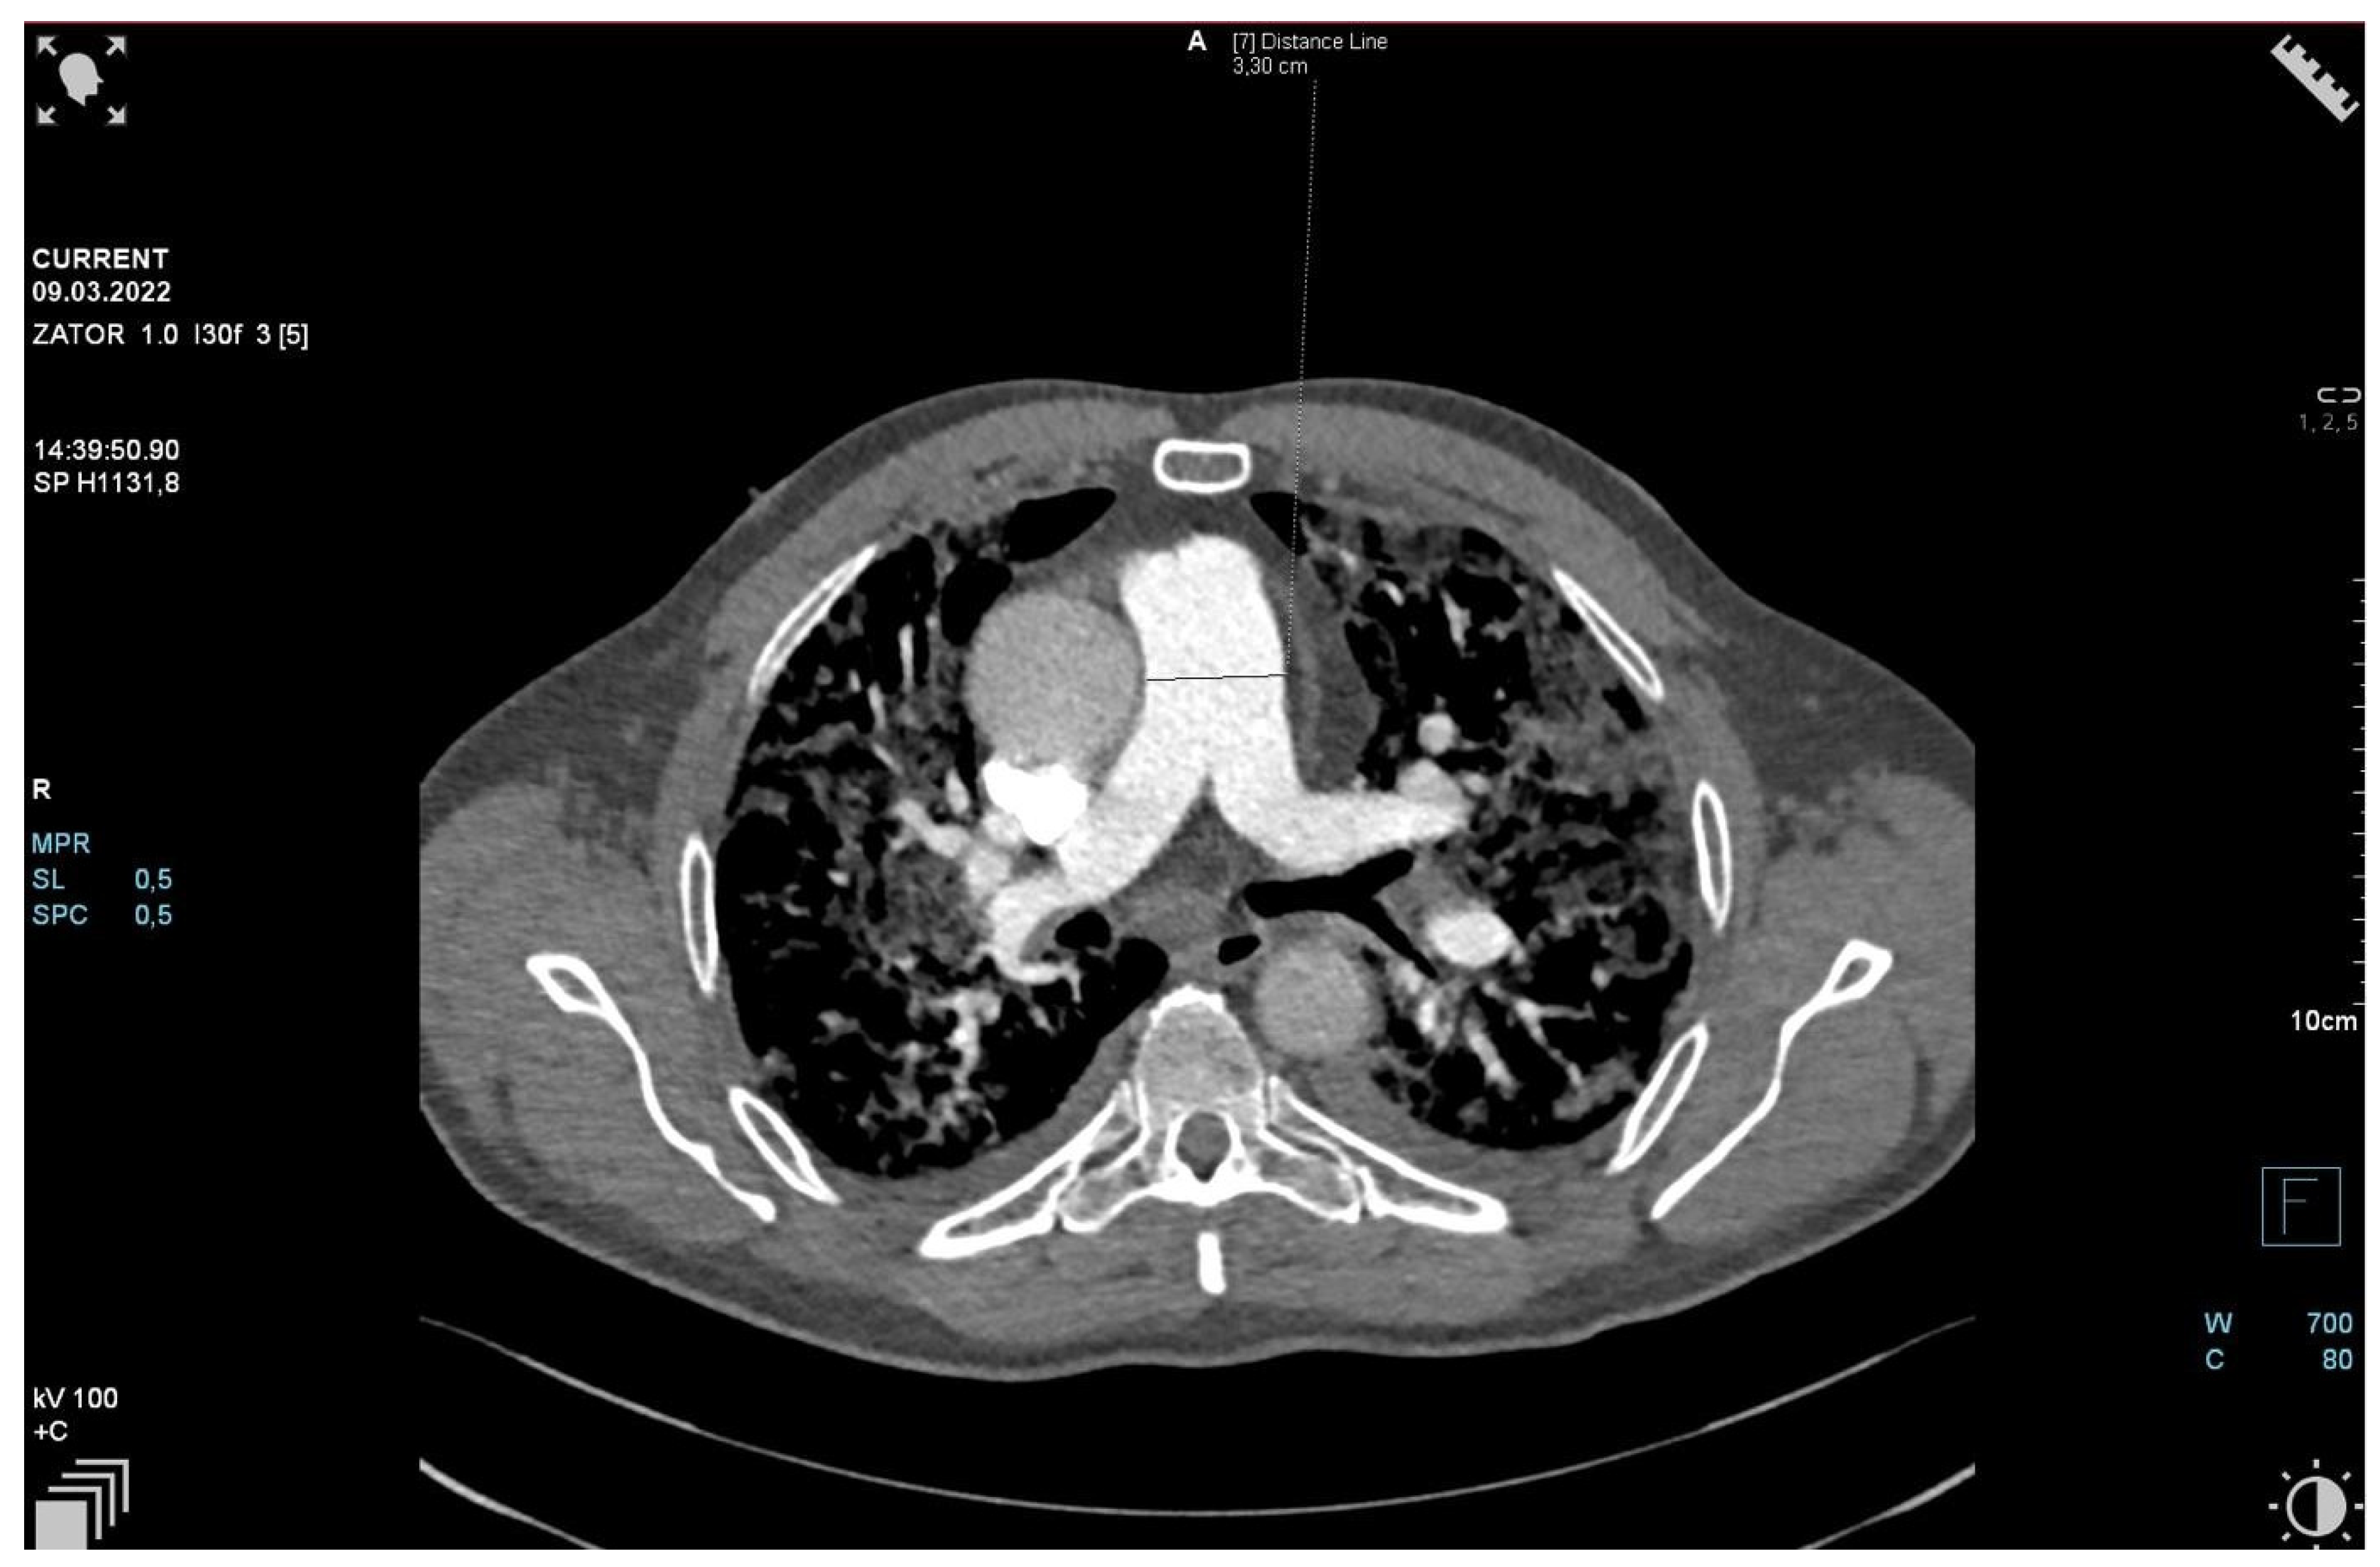

The patient required oxygen therapy, and initially, due to a lack of diagnosis, he received empirically broad-spectrum antibiotics (meropenem, linezolide). On laboratory testing, a further increase in inflammatory and coagulation biomarkers (CRP, ferritin, interleukin-6, D-Dimer, fibrinogen) was observed. Blood cultures as well as a respiratory PCR multitest were negative. Due to the dynamic increase in D-dimers and the elevation of cardiac biomarkers (BNP, NT-proBNP) along with dyspnea, an angio-CT was performed. It excluded pulmonary embolism, but it revealed widening of the pulmonary trunk and pulmonary arteries, as well as alveolar compaction in both lungs and bilateral pleural effusion. Pulmonary edema was diagnosed (Figure 2, Figure 3 and Figure 4).

Figure 2.

Angio-CT scan.